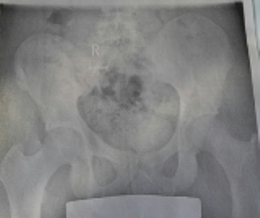

- Beckenschiefstand (Bild im Anhang)

Ansicht von vorne

20151219_150925-1.jpg (28 KiB) 10877 mal betrachtet

Es wurde ein Beckenschiefstand von 1,6cm gemessen.

Die Beinlängendifferenz sei sowohl funtionell als auch anatomisch bedingt.

Er hat mir dafür eine einseitige Schuherhöhung in Höhe von 0,5 cm verschrieben, welche ich so oft wie möglich tragen soll, da sie die Skoliose etwas optisch verbessert.